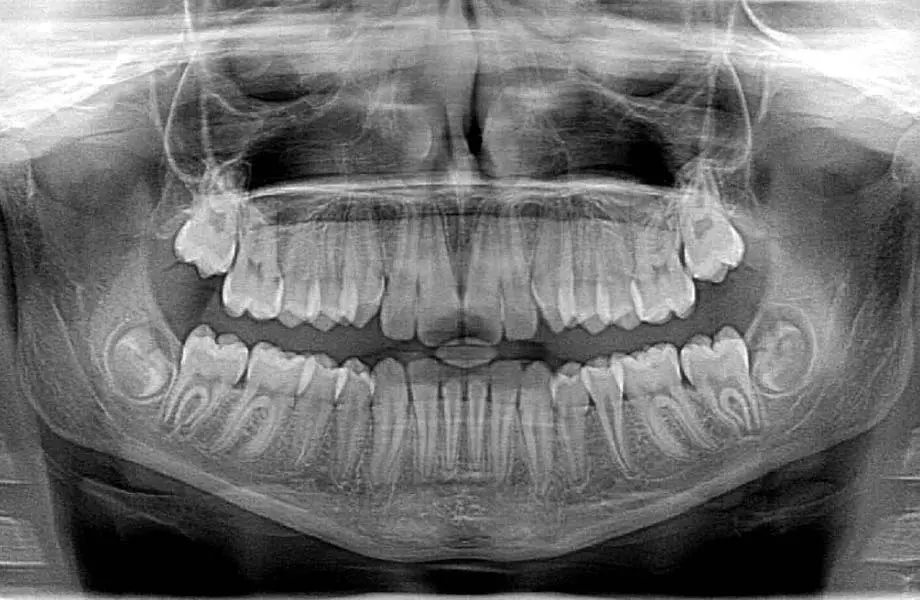

A visual dental exam only shows part of the picture. Many of the most significant dental problems, such as decay between teeth, bone loss from gum disease, or an infection at the root of a tooth, begin completely hidden from view. Dental X-rays (also called radiographs) are an essential diagnostic tool that allows us to see beneath the surface of your gums and enamel. They are, without a doubt, one of the most important components of a thorough and comprehensive dental examination, enabling us to catch problems early when they are easier and less expensive to treat.

Without the detailed view provided by an X-ray, a significant amount of your oral health would be left to guesswork. X-rays are a non-invasive way for us to accurately diagnose conditions that would otherwise go unnoticed until they become severe and painful.

Specifically, dental X-rays allow us to detect:

Cavities between teeth and underneath existing fillings.

Bone loss is associated with advanced gum disease (periodontitis).

Infections or abscesses at the tip of a tooth's root.

Impacted teeth, such as wisdom teeth, that are trapped in the jaw.

Cysts, tumors, and other types of abnormalities.

Developmental issues with the teeth and jaw in children.

We use different types of X-rays for different purposes, including bitewings during your check-up to look for cavities, and panoramic X-rays to see a broad overview of your entire jaw.